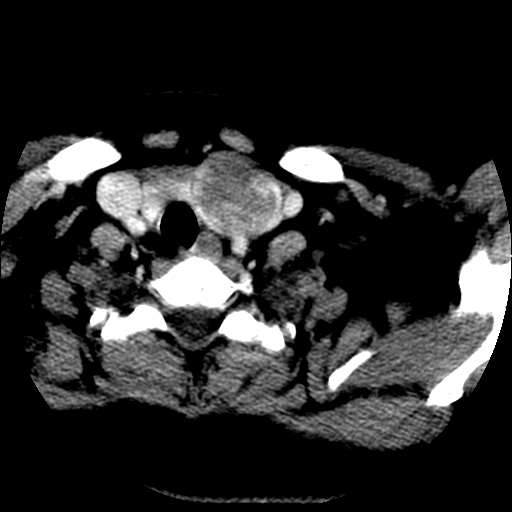

标题: CT25491:女,55岁,发现左侧甲状腺肿块一个月。 [打印本页]

标题: CT25491:女,55岁,发现左侧甲状腺肿块一个月。

女,55岁,发现左侧甲状腺肿块一个月,彩超示:甲状腺多发结节伴左叶结节液化。

左右叶都有,峡部也受累,有钙化,考虑结甲可能性大。

考虑右叶结节性甲状腺肿,伴左叶钙化。主要(1)密度均匀,边境清。(2)病灶与血管界限清。